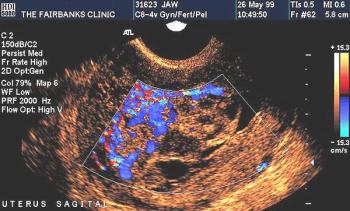

This is a confirmed case of scar ectopic pregnancy. Yesterday, I carried out this exam in an emergency room, without much time to perform an adequate sonogram, the patient did not feel good with “cramps” but no signs of bleeding.